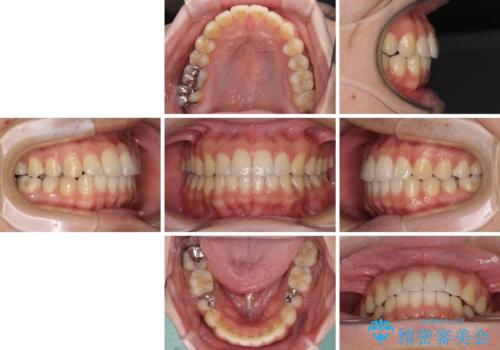

- 矯正治療の後戻りを気にして来院された患者様です。

後戻りは軽微でしたので、インビザライン・ライトにより矯正治療を行うこととしました。

再矯正後の後戻りを防ぐため、歯列排列後に、下顎前歯はワイヤーによる固定を行いました。

下顎前歯の歯列を動かないようにしておくことで、上顎前歯の後戻り防止にも効果を発揮します。